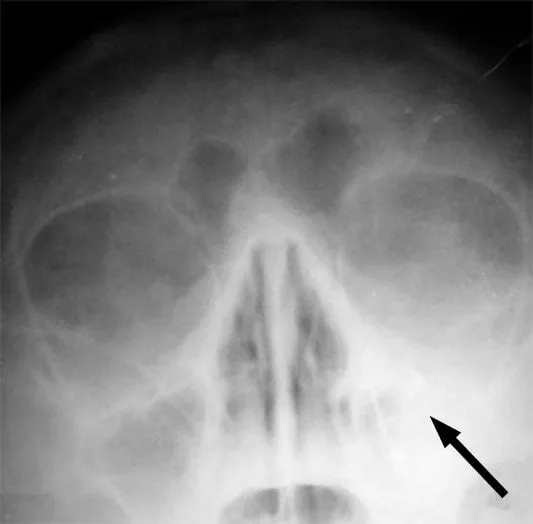

Photo : radiographie d'une sinusite maxillaire gauche marquée d'une flèche

La sinusite est une inflammation des sinus, ces petites cavités osseuses situées au niveau du visage et du crâne. Ces cavités sont creusées dans le massif osseux de la face et elles communiquent avec les fosses nasales par un orifice étroit.

Les sinus se développent progressivement au cours de l’enfance. Seuls les sinus ethmoïdaux sont présents dès la naissance, les sinus maxillaires apparaissent généralement entre l’âge de trois et quatre ans, les frontaux vers dix ans et les sphénoïdaux au cours de la puberté. La sinusite ethmoïdale chez l'enfant associée à un gonflement des paupières nécessite un traitement d'urgence.